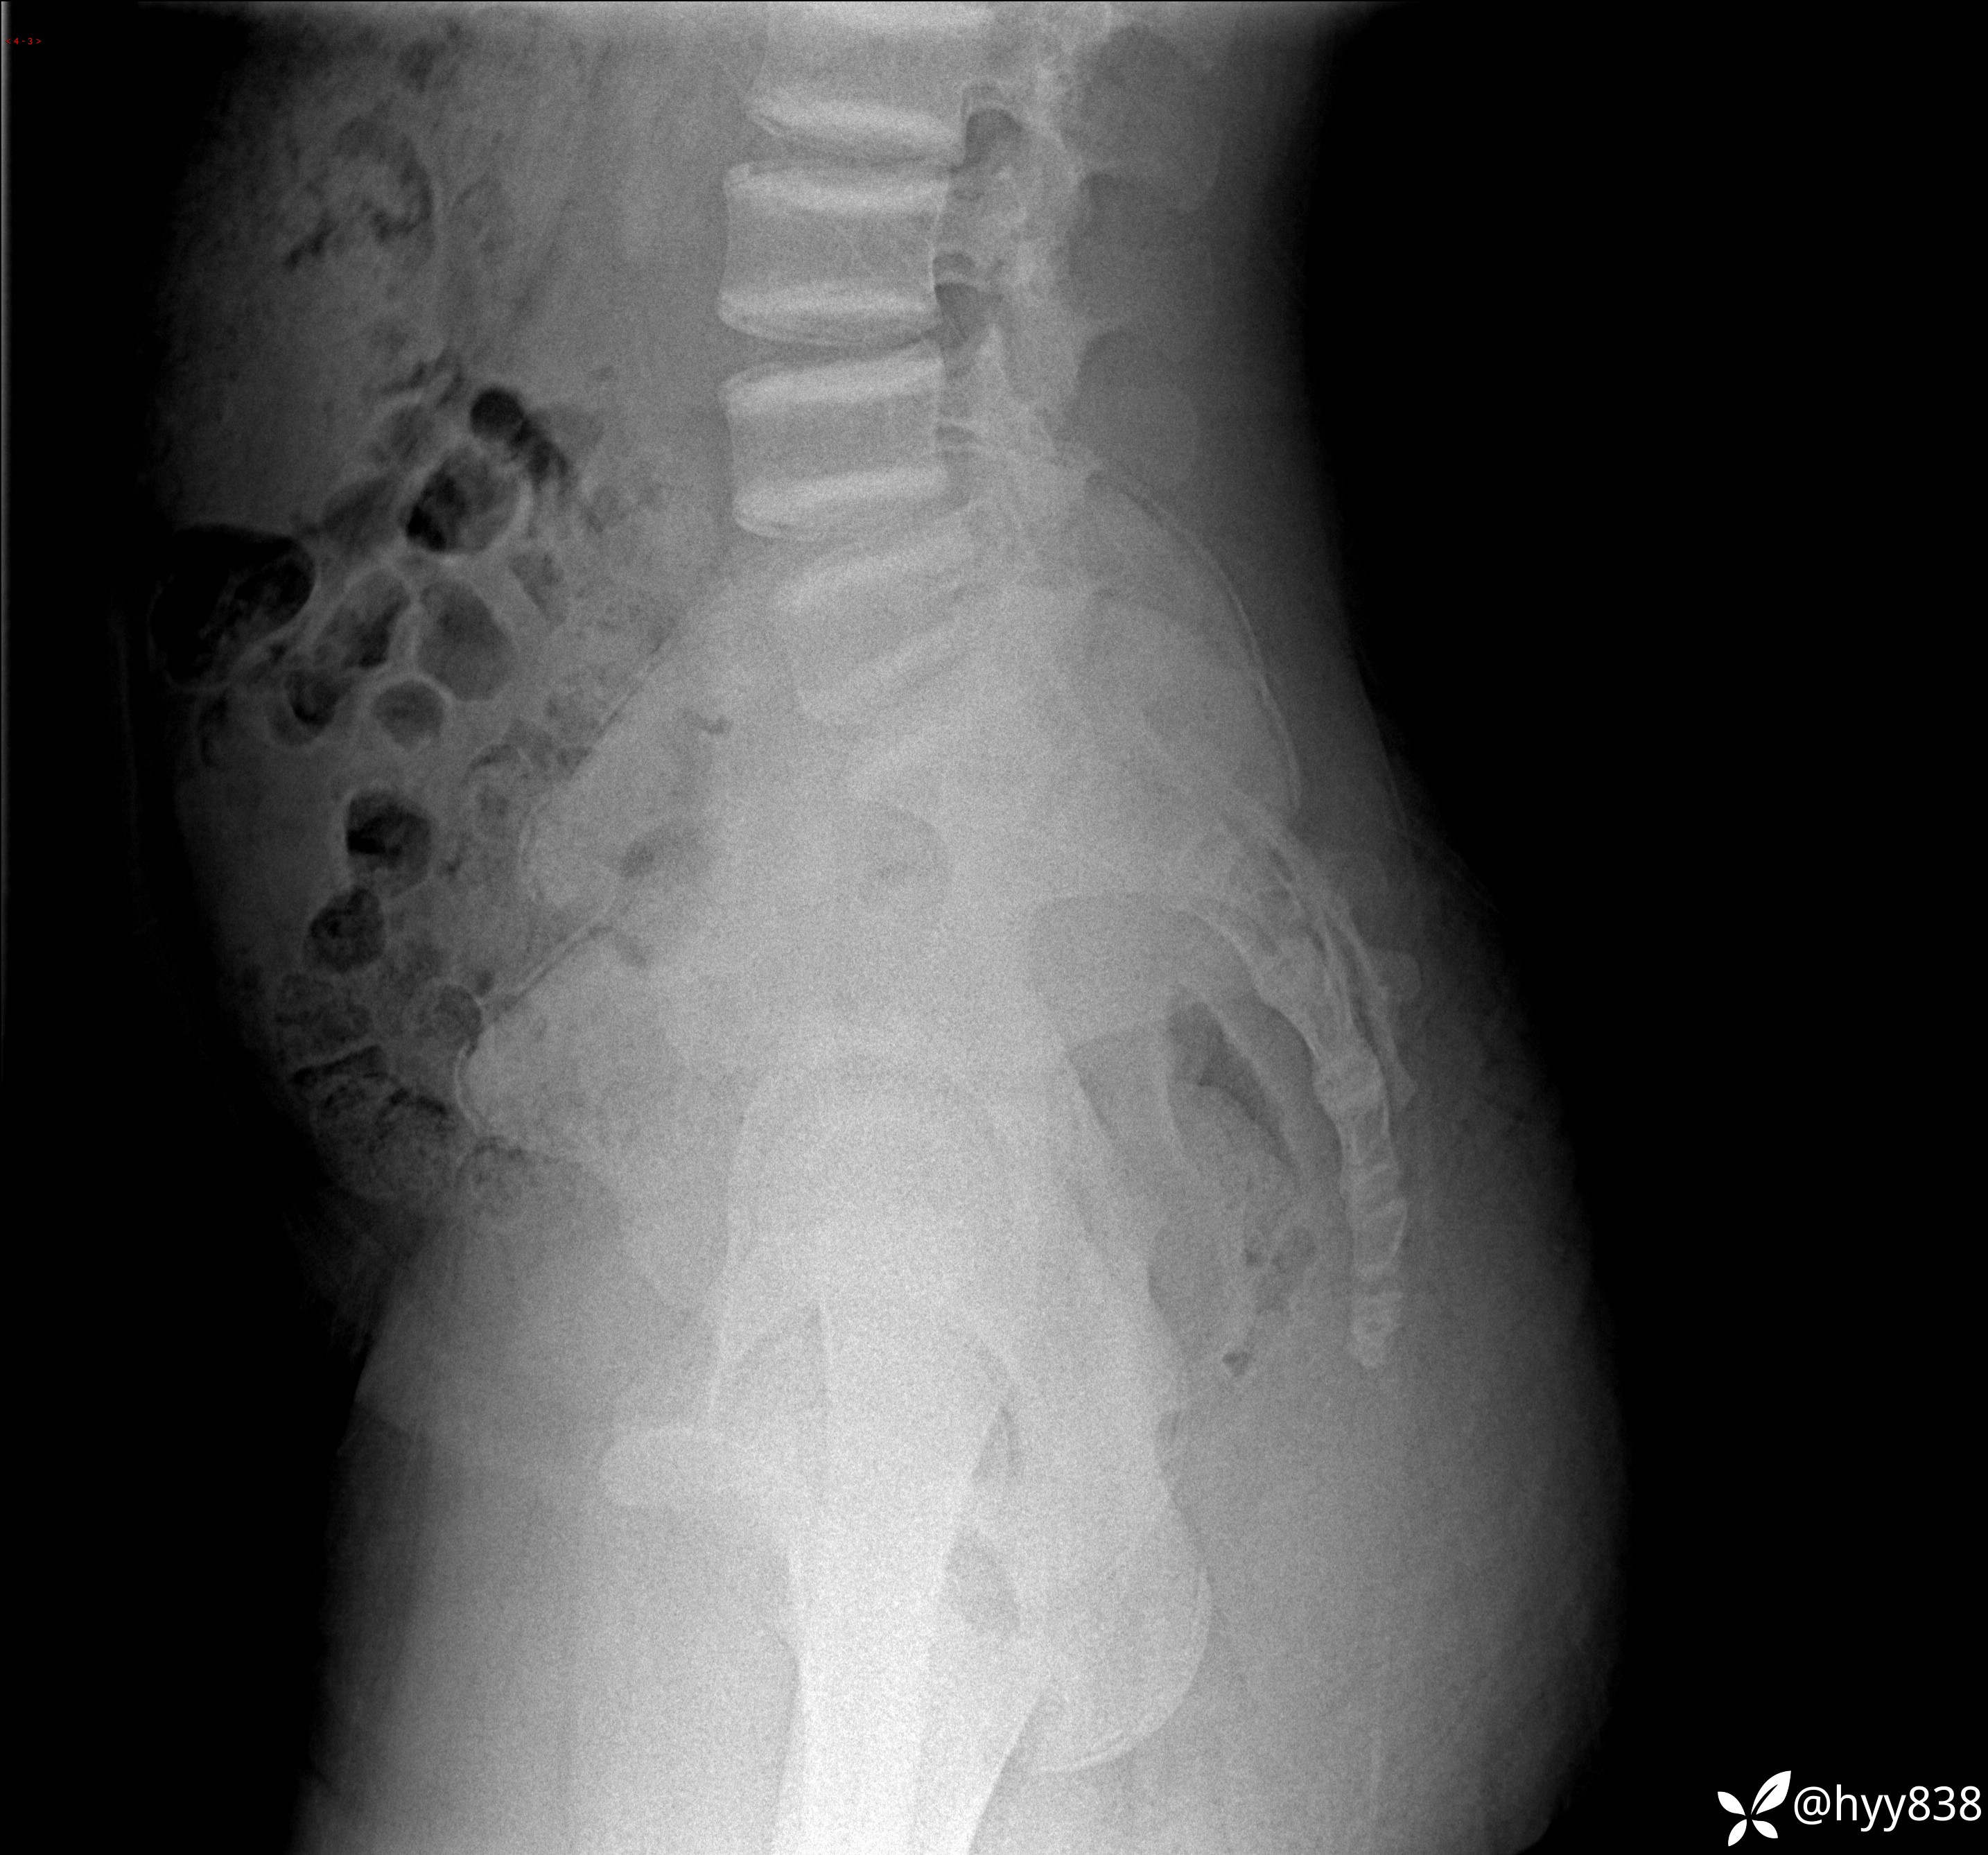

颈椎、胸椎、腰椎正侧位片

img